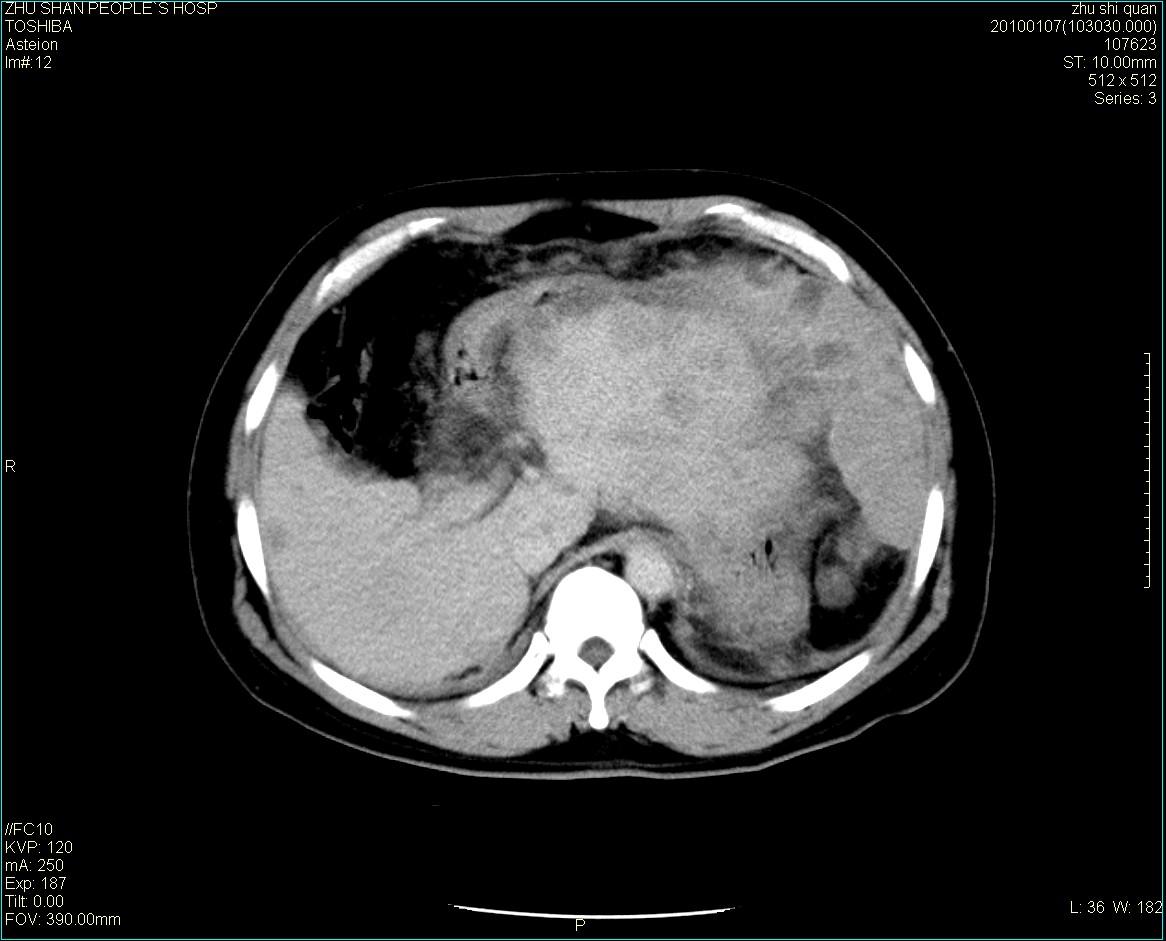

男性病人 肝ca两次术后,今日复查。

多发转移

肝、脾多发转移灶,胸腔积液

1)肝癌并多发性转移。2)双侧胸腔积液(以左侧为甚)伴左下部分肺萎陷。

肝癌术后复发,考虑肝、脾多发转移。

肝癌术后复发,肝内、脾脏、腹膜后及腹膜多发转移,腹水,双侧胸腔积液(以左侧为甚)伴左下膨胀不全。

肝、脾多发转移灶,胸腔积液。

肝癌术后复发,肝内、脾脏、腹膜后及腹膜多发淋巴结转移,腹水,双侧胸腔积液。